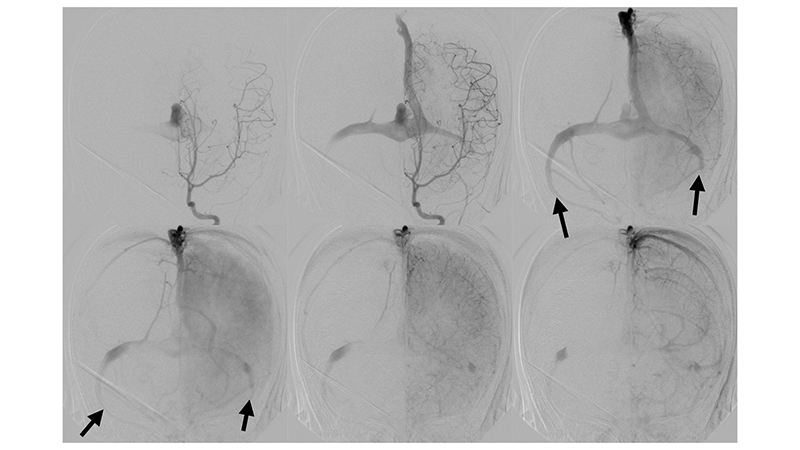

- Καθετηριασμός και εμβολισμός με κυανοακρυλική κόλλα θαλαμοδιατιτραινόντων κλάδων.

- Καθετηριασμός και εμβολισμός με κυανοακρυλική κόλλα υποεπενδυματικών κλάδων.

- Καθετηριασμός και εμβολισμός με κυανοακρυλική κόλλα οπισθιοπλαγίων χοριοειδών κλάδων.